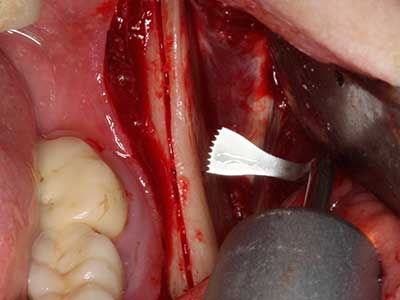

Fig. 28: En el marco de la retirada del metal se realiza la separación de la parte basal del mentón manteniendo el suministro sanguíneo lingual con el Piezomed.

Fig. 29: Desplazamiento delantero del mentón en 5 mm y fijación mediante dos placas de osteosíntesis (KLS Martin). En el borde se aprecian los dos nervios mentonianos.